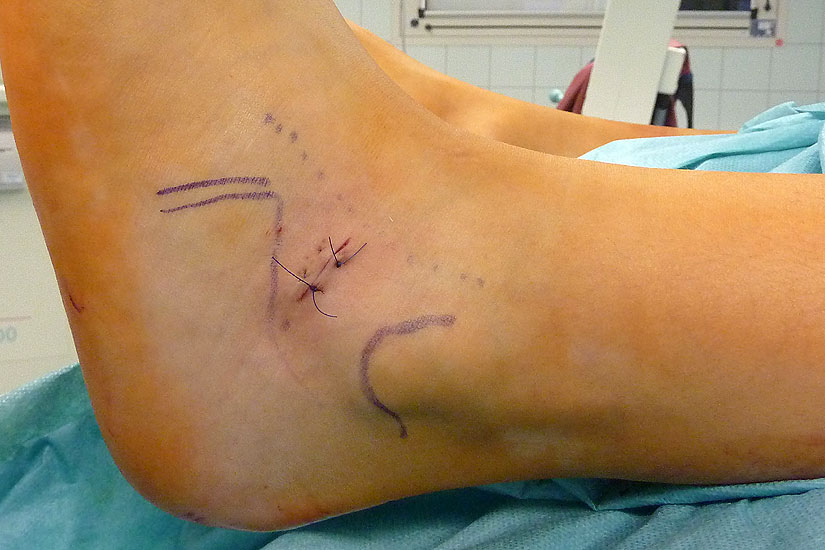

Röntgenkontrolle d.p. und seitlich unter Belastung nach 2, 6 und 12 Wochen und Beurteilung des Ergebnisses im Vergleich mit den präoperativen Bildern.

Abbildung 15

• Röntgenkontrolle d.p. und seitlich unter Belastung nach 2, 6 und 12 Wochen und Beurteilung des Ergebnisses im Vergleich mit den präoperativen Bildern (Abb.15).